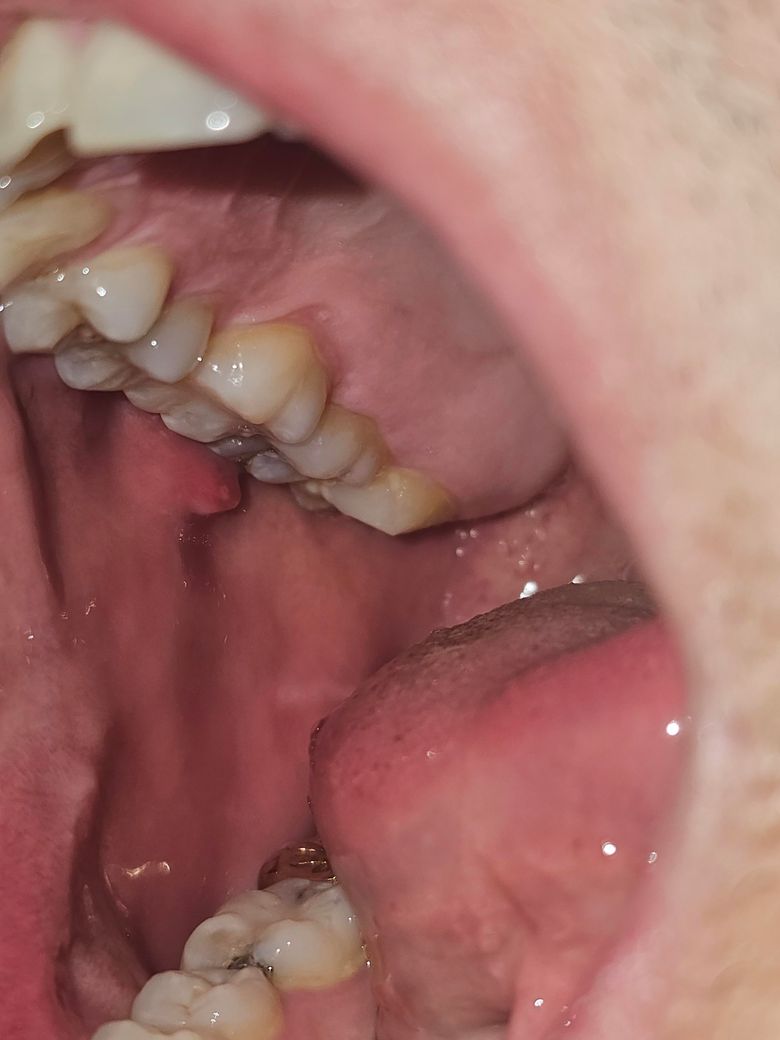

볼안쪽이 부어서 구내염같은게 생겼는데 그냥 구내염인가요?

몇일전에 혓바닥으로 볼을 만져보니 뭐가 튀어나와있습니다.

이게 지금은 끝에 구내염처럼 하얗게 되었는데 그냥 구내염인지 아니면 섬유종? 인지 궁금함키다.

• 1번 째 사진

해당 부분은 볼살이 치아에 씹히면서 자극에 의해서 부은 것으로 보이며 가라앉을 것 같습니다.

구내염은 아니며 볼살이 씹혀서 생긴 자국입니다. 주로 선상으로 생기며 그냥두면 없어집니다.

구내염은 아니고 볼살이 치아에 씹혀서 그런거 같습니다. 통증이 잇거나 그렇지 않으면 크게 신경쓰지 않으셔도 됩니다.

말씀하신 섬유종과 함께 구내염의 양상도 동반된 것 같습니다. 치과가서 조직검사를 해보시고 일반적인 섬유종이라면 절제 합니다.